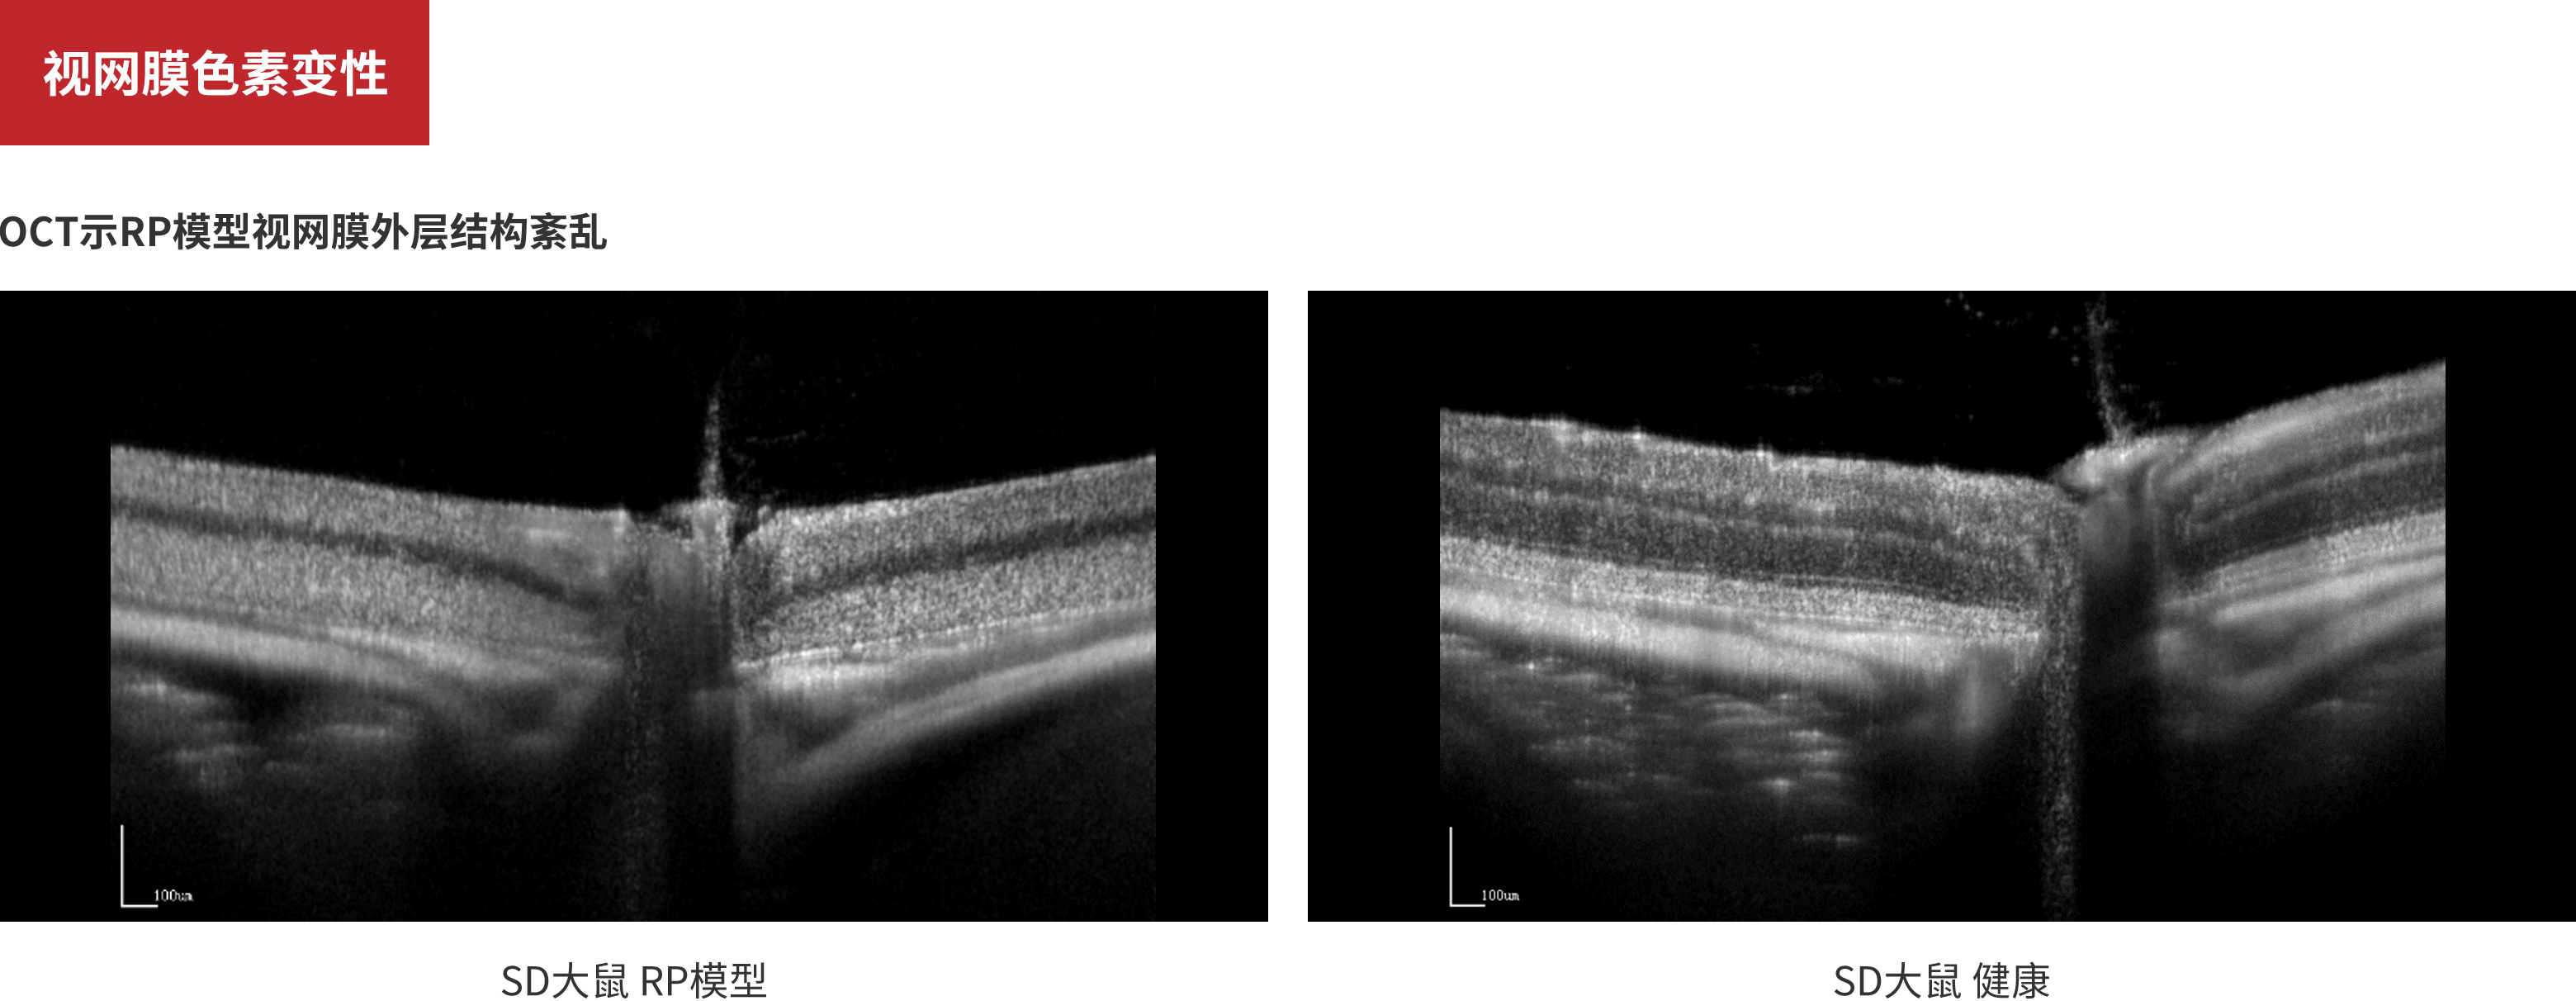

视网膜色素变性